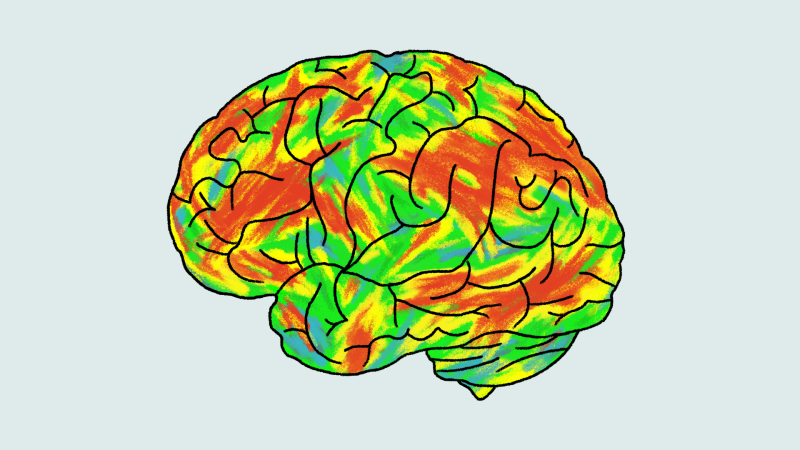

What experts say about taking psilocybin as an alternative treatment for depression

The matchup: Two doses of psilocybin, the active ingredient in “magic mushrooms,” against a six-week course of the popular antidepressant escitalopram, often sold as Lexapro or Cipralex. Escitalopram is one…